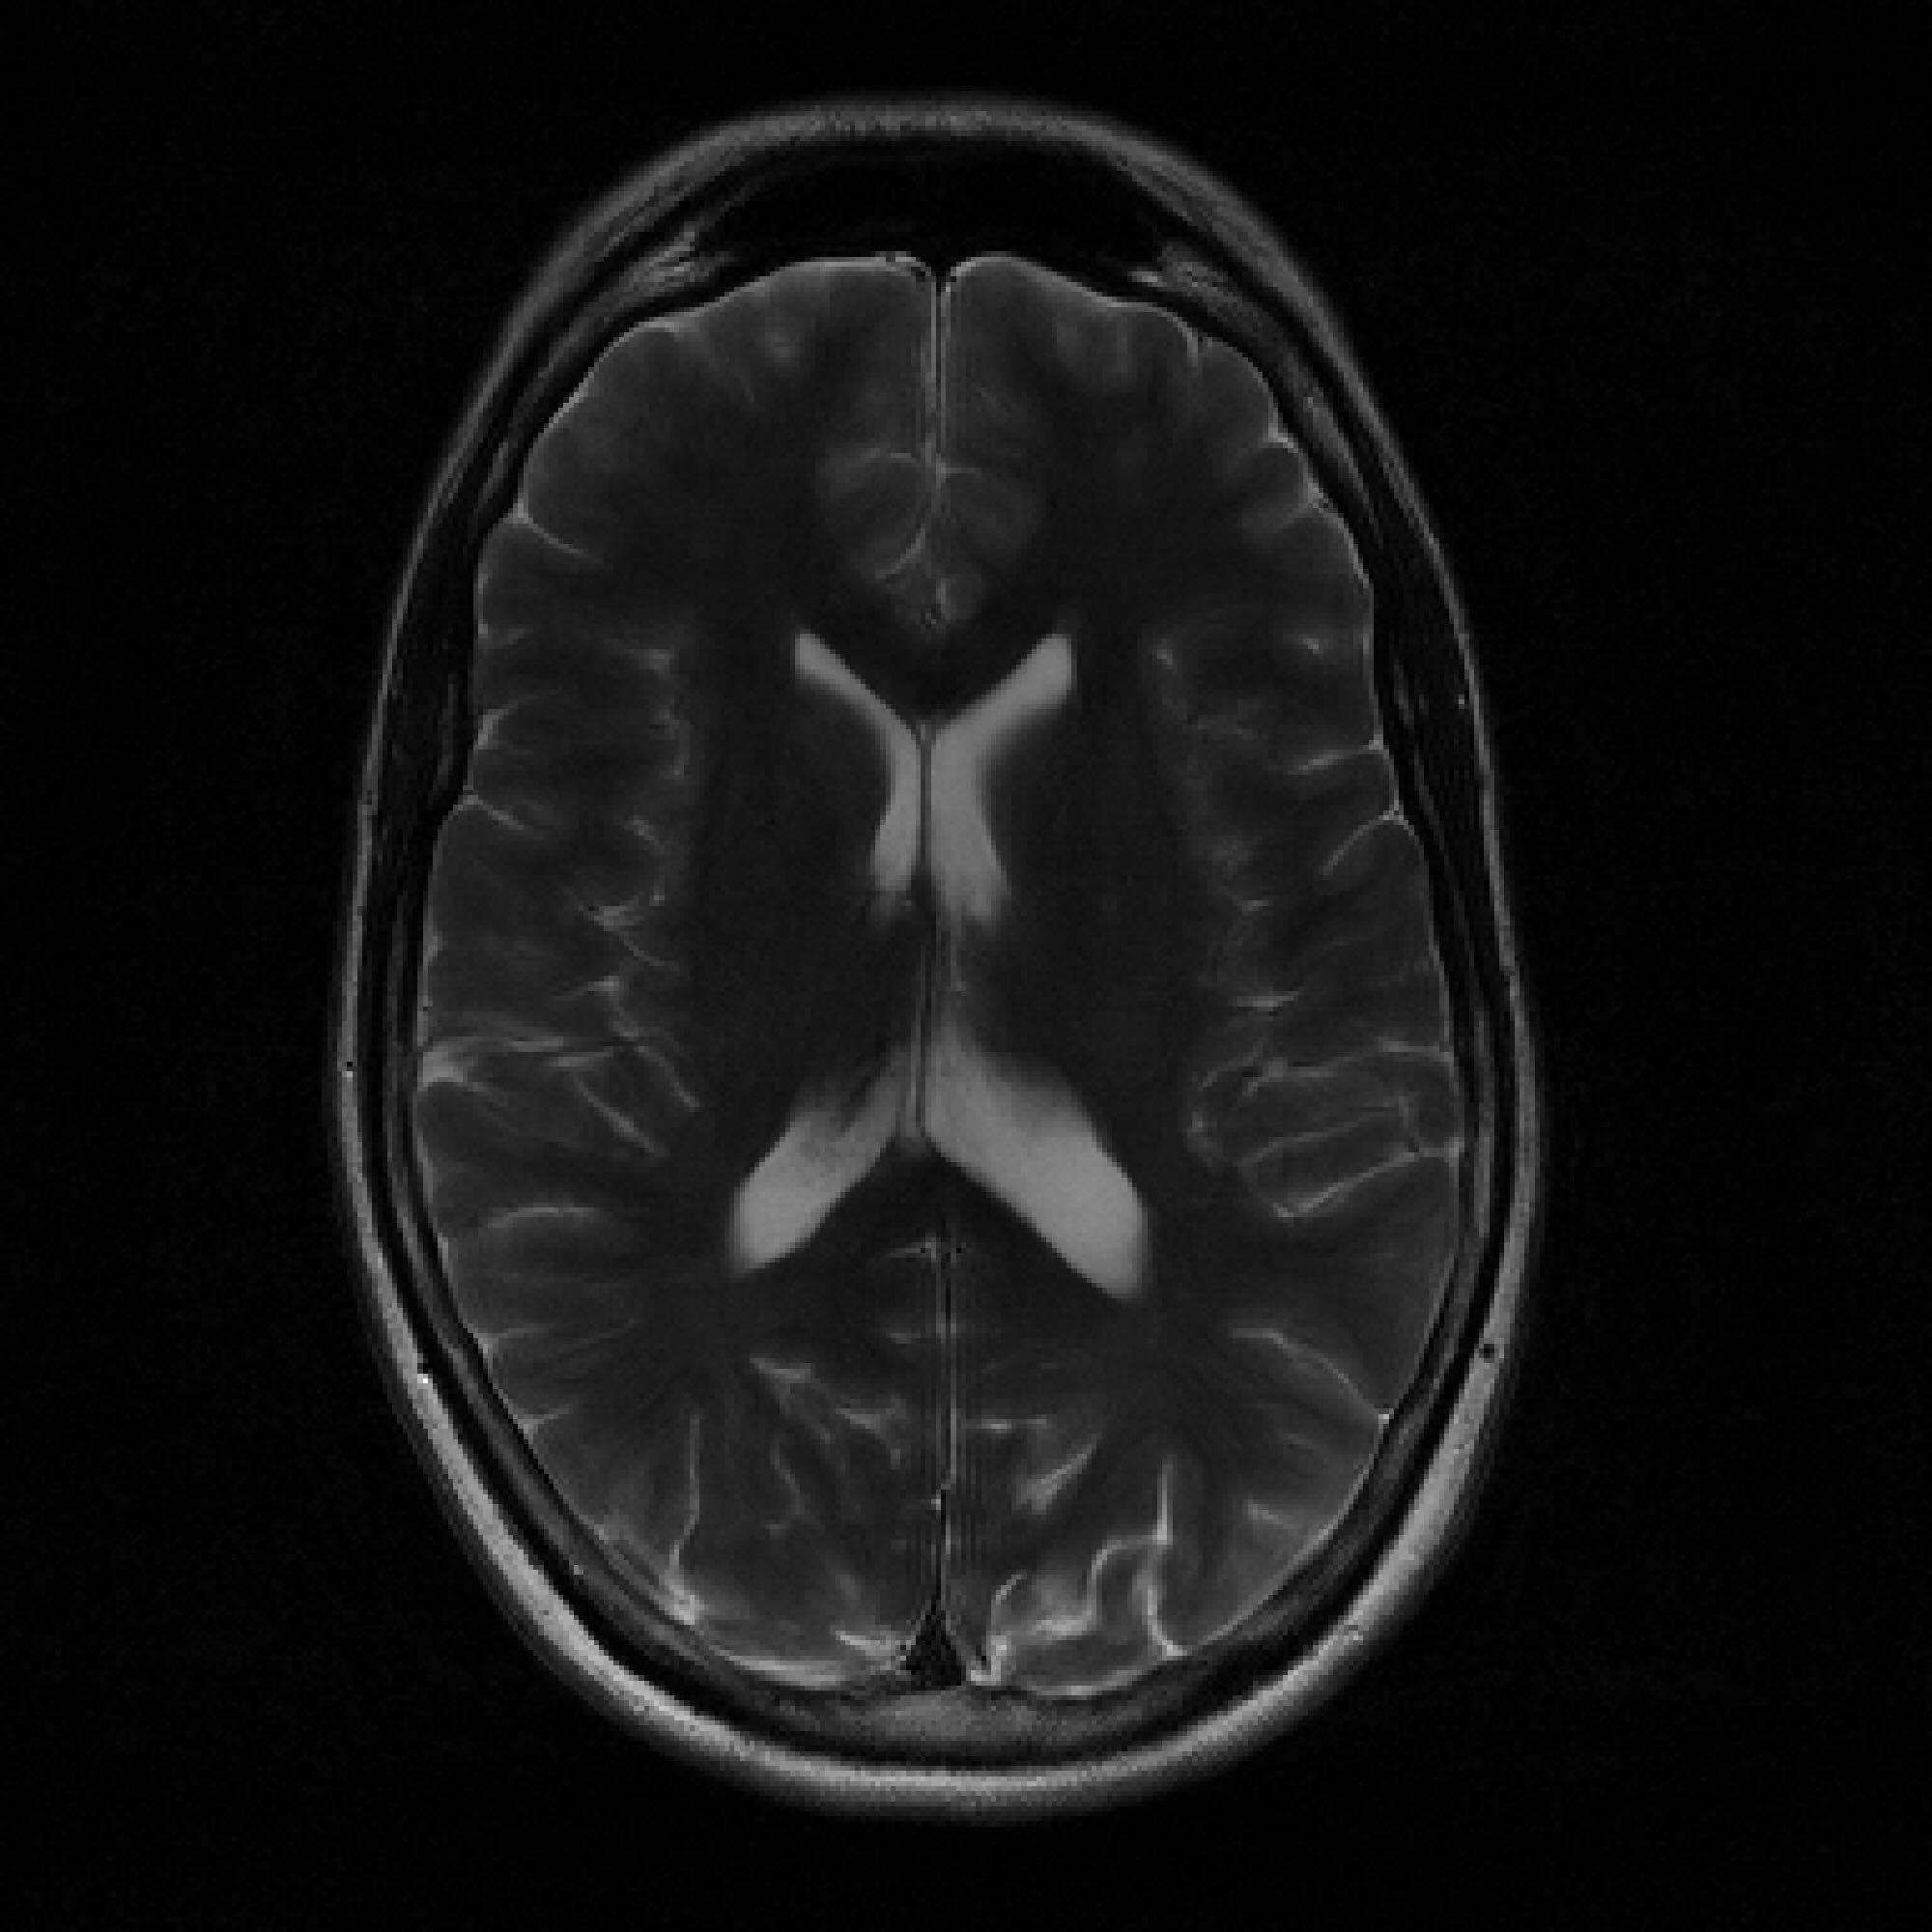

T2-Axial T2-Axial T2-Axial FLAIR T1

Refer to caption  Refer to caption  Refer to caption   Refer to caption  Refer to caption  Refer to caption   Refer to caption  Refer to caption  Refer to caption   Refer to caption  Refer to caption  Refer to caption   Refer to caption  Refer to caption  Refer to caption

Figure 6: Dataset Size S=200S=200, Undersampling Rate R=7R=7 Inset Comparisons. The top row shows the ground truth images. The middle row shows the FastMRI-EDM reconstructions. The bottom row shows the PaDIS-MRI reconstructions, which exhibit slight perceptual improvements at the insets.